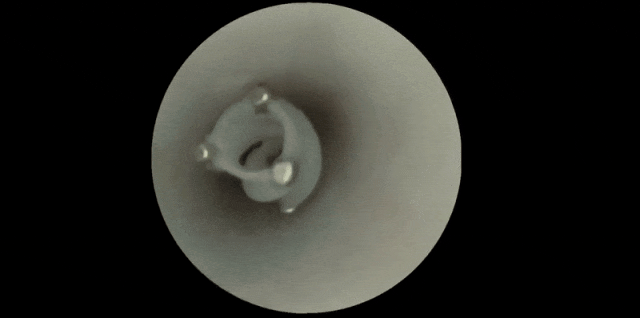

这一次,团队保留了其中最关键的结构——螺旋状的侧翼、中空的管道和开槽的外壁,并将原本指甲盖大小的装置缩小到了直径与长度仅几毫米,恰好适合在直径3~5毫米的大脑血管中穿行。

机器人进入血管后,外部施加的旋转磁场会驱动它快速旋转。特殊的中空设计使得它在前进时会产生负压,液体从前端吸入,再从后端和侧槽喷出,从而推动机器人前行。

机器人的特殊结构,使其能在血管中快速前进 | 参考文献[2]